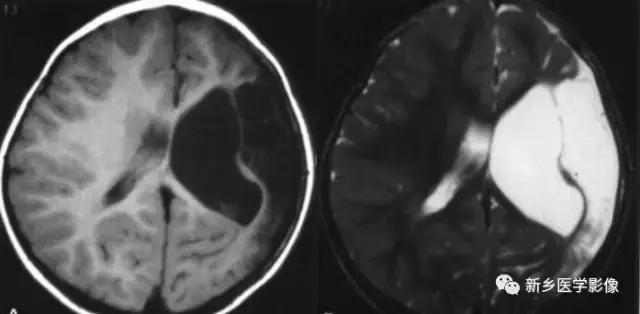

(2)脑裂畸形:胚胎期脑的发育经历6个主要阶段:①背侧诱导阶段;③腹侧诱导阶段;③神经增生阶段;④神经元移行阶段;⑤组织形成阶段;⑥髓鞘形成阶段。脑裂畸形发生在神经元移行阶段。脑裂畸形可累及一侧或双侧大脑半球,脑裂畸形位于侧面.常累及中央前、后回区偶尔位于大脑半球的其他部位。脑裂畸形的裂隙可以很窄,裂隙两侧灰质紧密相贴,称闭合型。裂隙也可以很宽,中间为脑脊液,分离型。

分离型脑裂畸形需要与脑穿通畸形囊肿鉴别.脑裂畸形的裂隙两旁一定为一灰质结构,而脑穿通畸形囊肿周围无脑灰质包绕。裂隙两旁是否为灰质结构是区别脑裂畸形与脑穿通畸形囊肿的可靠征象。裂隙两侧的灰质可不正常,可呈多小脑回样。脑裂畸形也可合并脑灰质异位。

分离型在CT很容易显示.闭合型有时容易漏诊.MRI对裂隙两侧的灰质结构容易辨认。脑裂畸形常合并透明隔缺如.侧脑室扩大,脑裂畸形处脑室边缘不规则.常可见指向裂隙的裂或 三角形憩室存在。

临床上脑裂畸形常表现有癫痫发作,其他神经系统症状可从很轻微到很严重.主要取决于脑裂畸形使脑组织缺损的严重程度。单侧闭合型脑裂畸形症状通常较轻,双侧分离型脑裂畸形症状较明显。